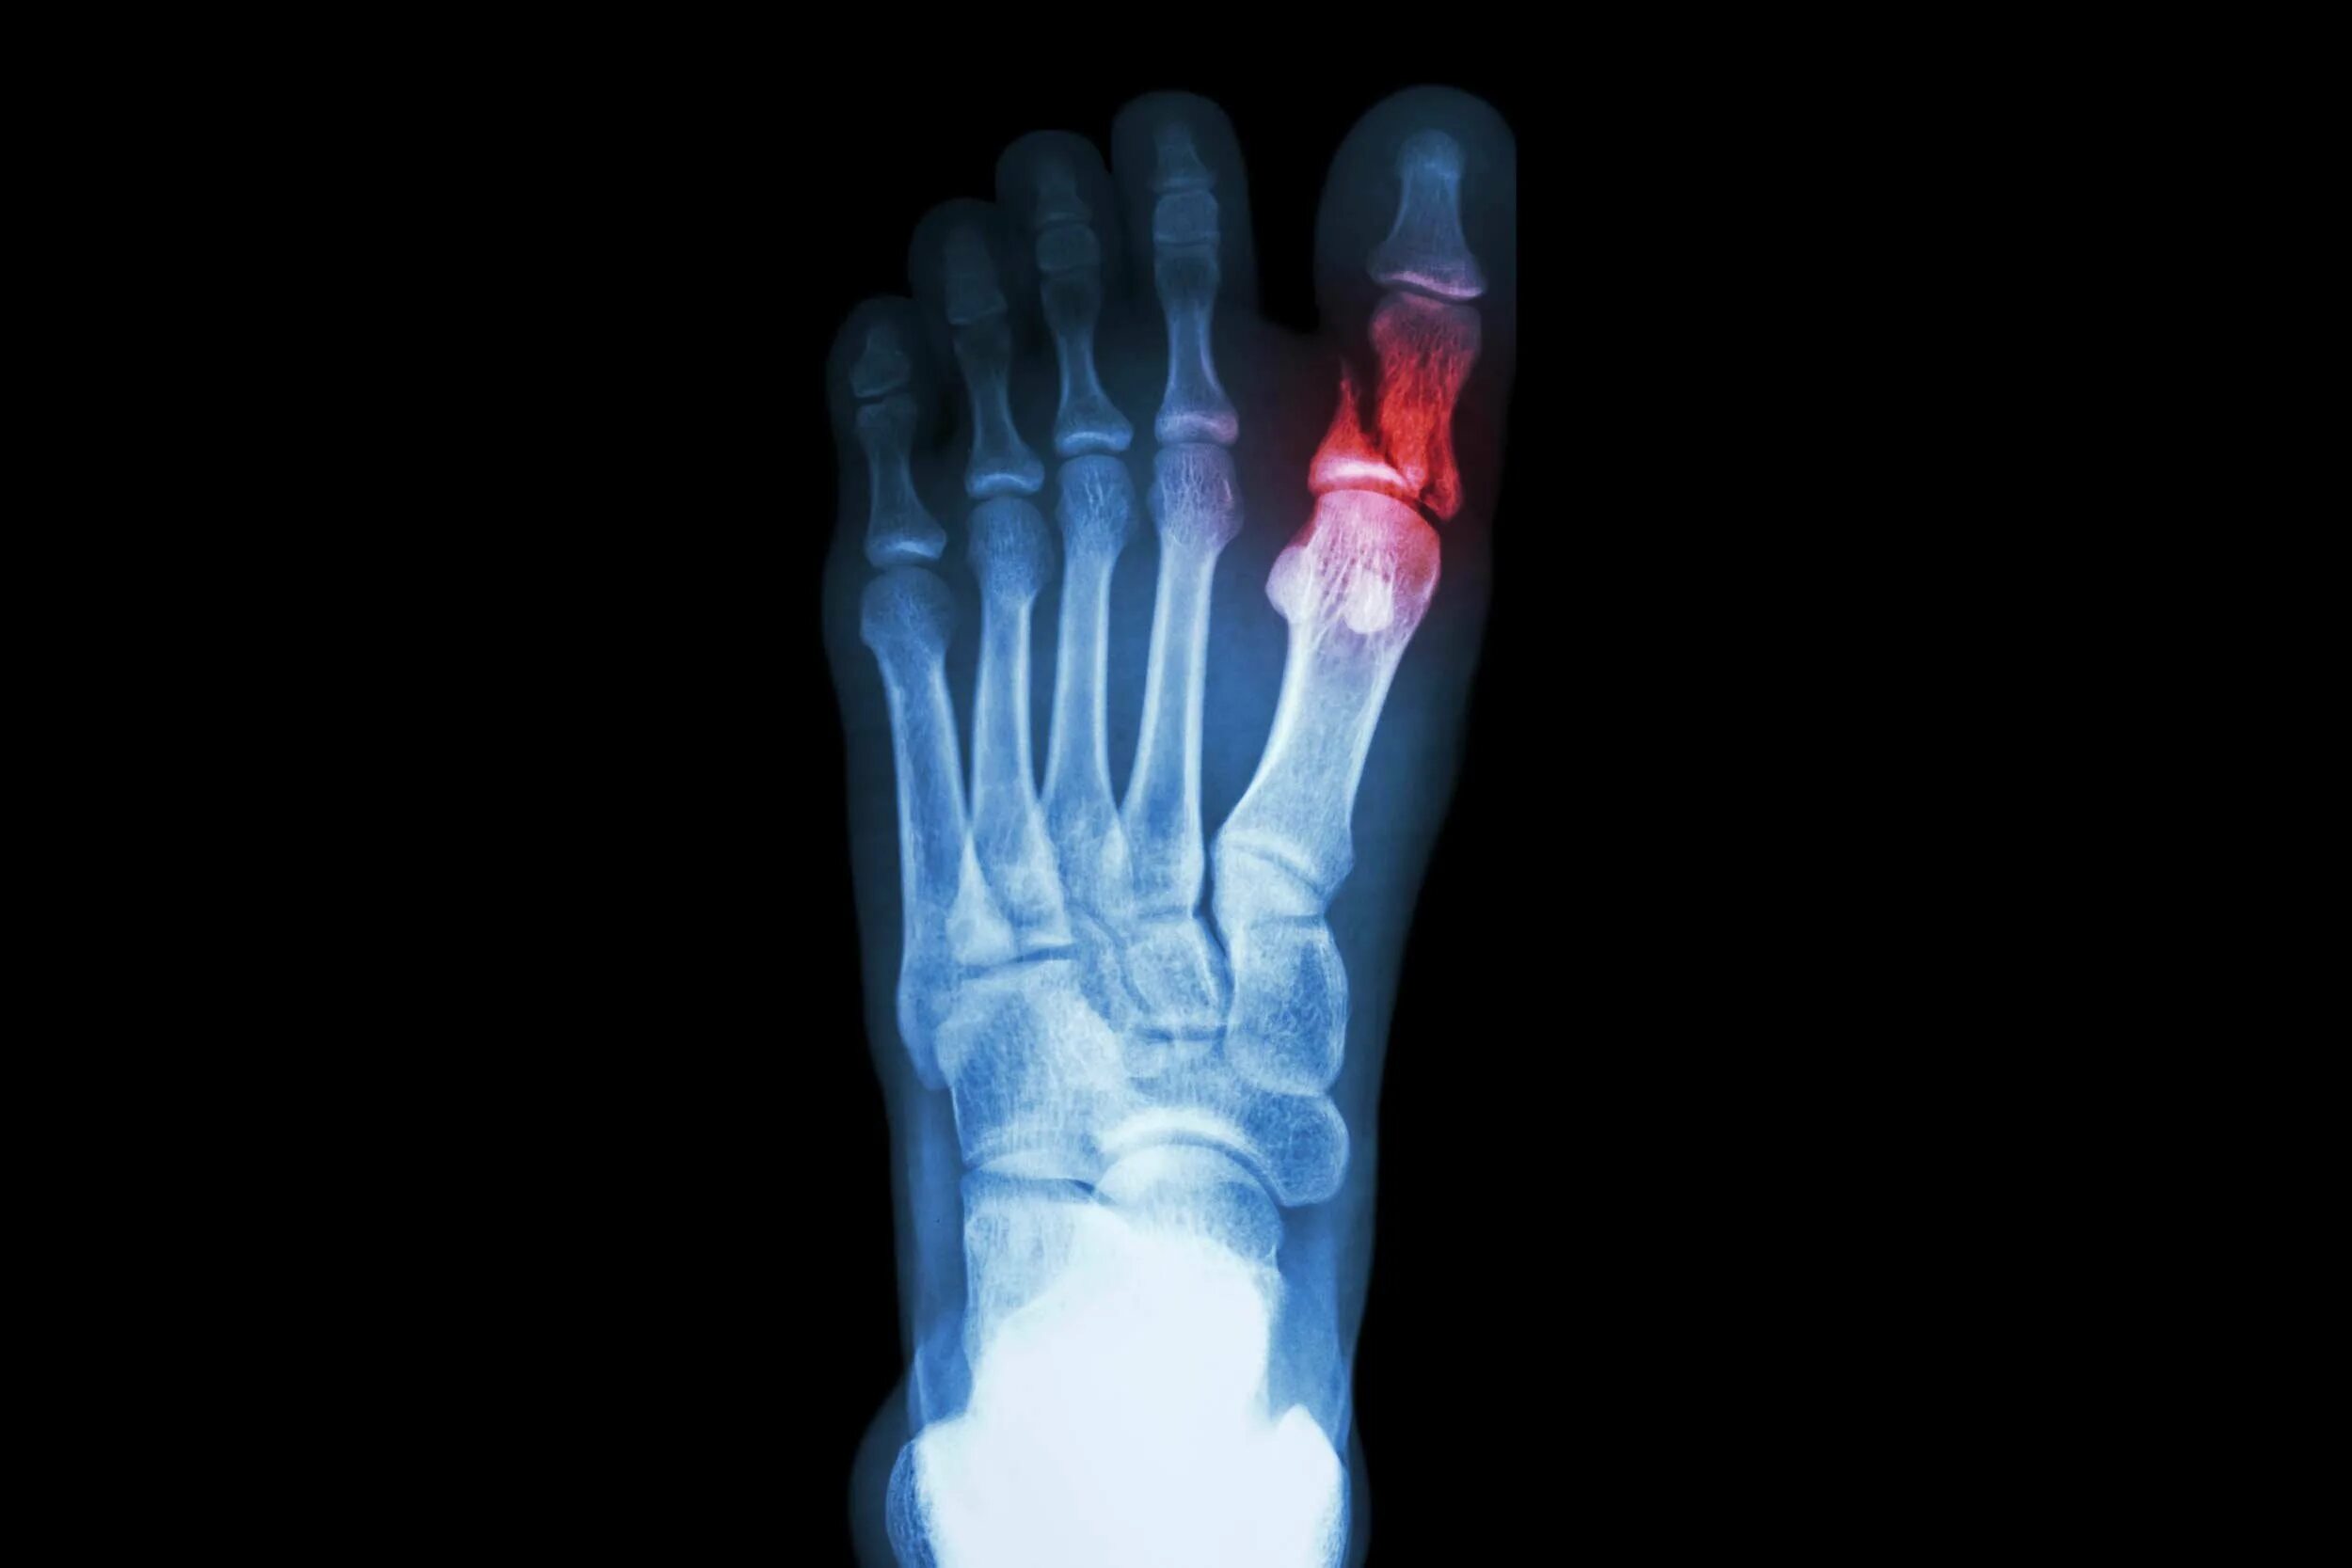

Как определить перелом стопы